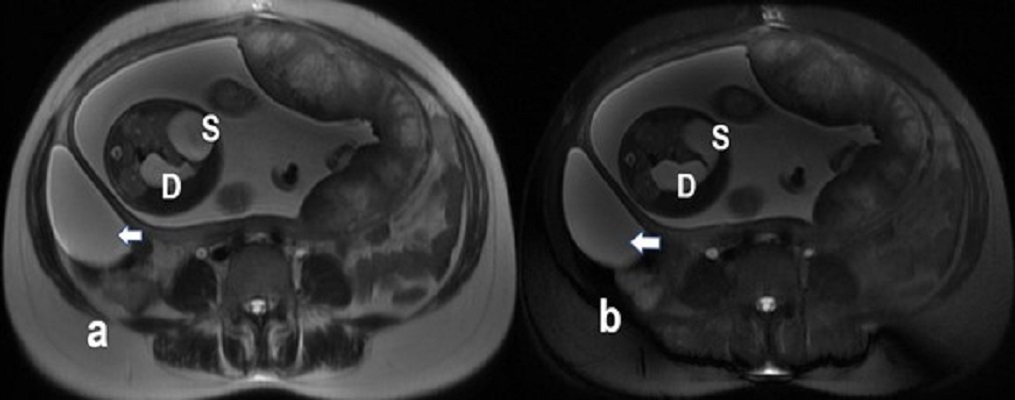

A 33-year-old Indian primigravida with a history of hypothyroidism and Rh isoimmunization came for routine antenatal ultrasonography at 28 weeks and 4 days of gestation. Her triplet or triple test was negative. In her previous ultrasonography, done at 12 weeks, fetal growth parameters were lagging behind LMP [last menstrual period] by 10 days. The present ultrasound showed mild polyhydramnios with an amniotic fluid index of 28, a single umbilical artery, preaxial polydactyly, and fetal growth retardation. The stomach and duodenum were dilated leading to a double bubble sign with a hyperechogenic band surrounding the fetal duodenum (Fig.1). Differential diagnosis of duodenal obstruction either due to annular pancreas, duodenal atresia/stenosis, or malrotation were given. A maternal right ovarian cyst (8.1 x 5.4 cm) was also documented. The fetal amniotic karyotype was normal, 46 XX. Fetal ECHO was also normal. Fetal MRI performed demonstrated dilated stomach and the duodenum giving double bubble sign (Fig.2).

Figure 2

Axial single-shot fast spin-echo with breath-hold (a) and fat-saturated (b) MR images confirming the ultrasound findings. Dilated fetal stomach (S) and duodenum (D) were seen. Maternal right ovarian cyst showed benign features with no evidence of septation or nodule (arrow)